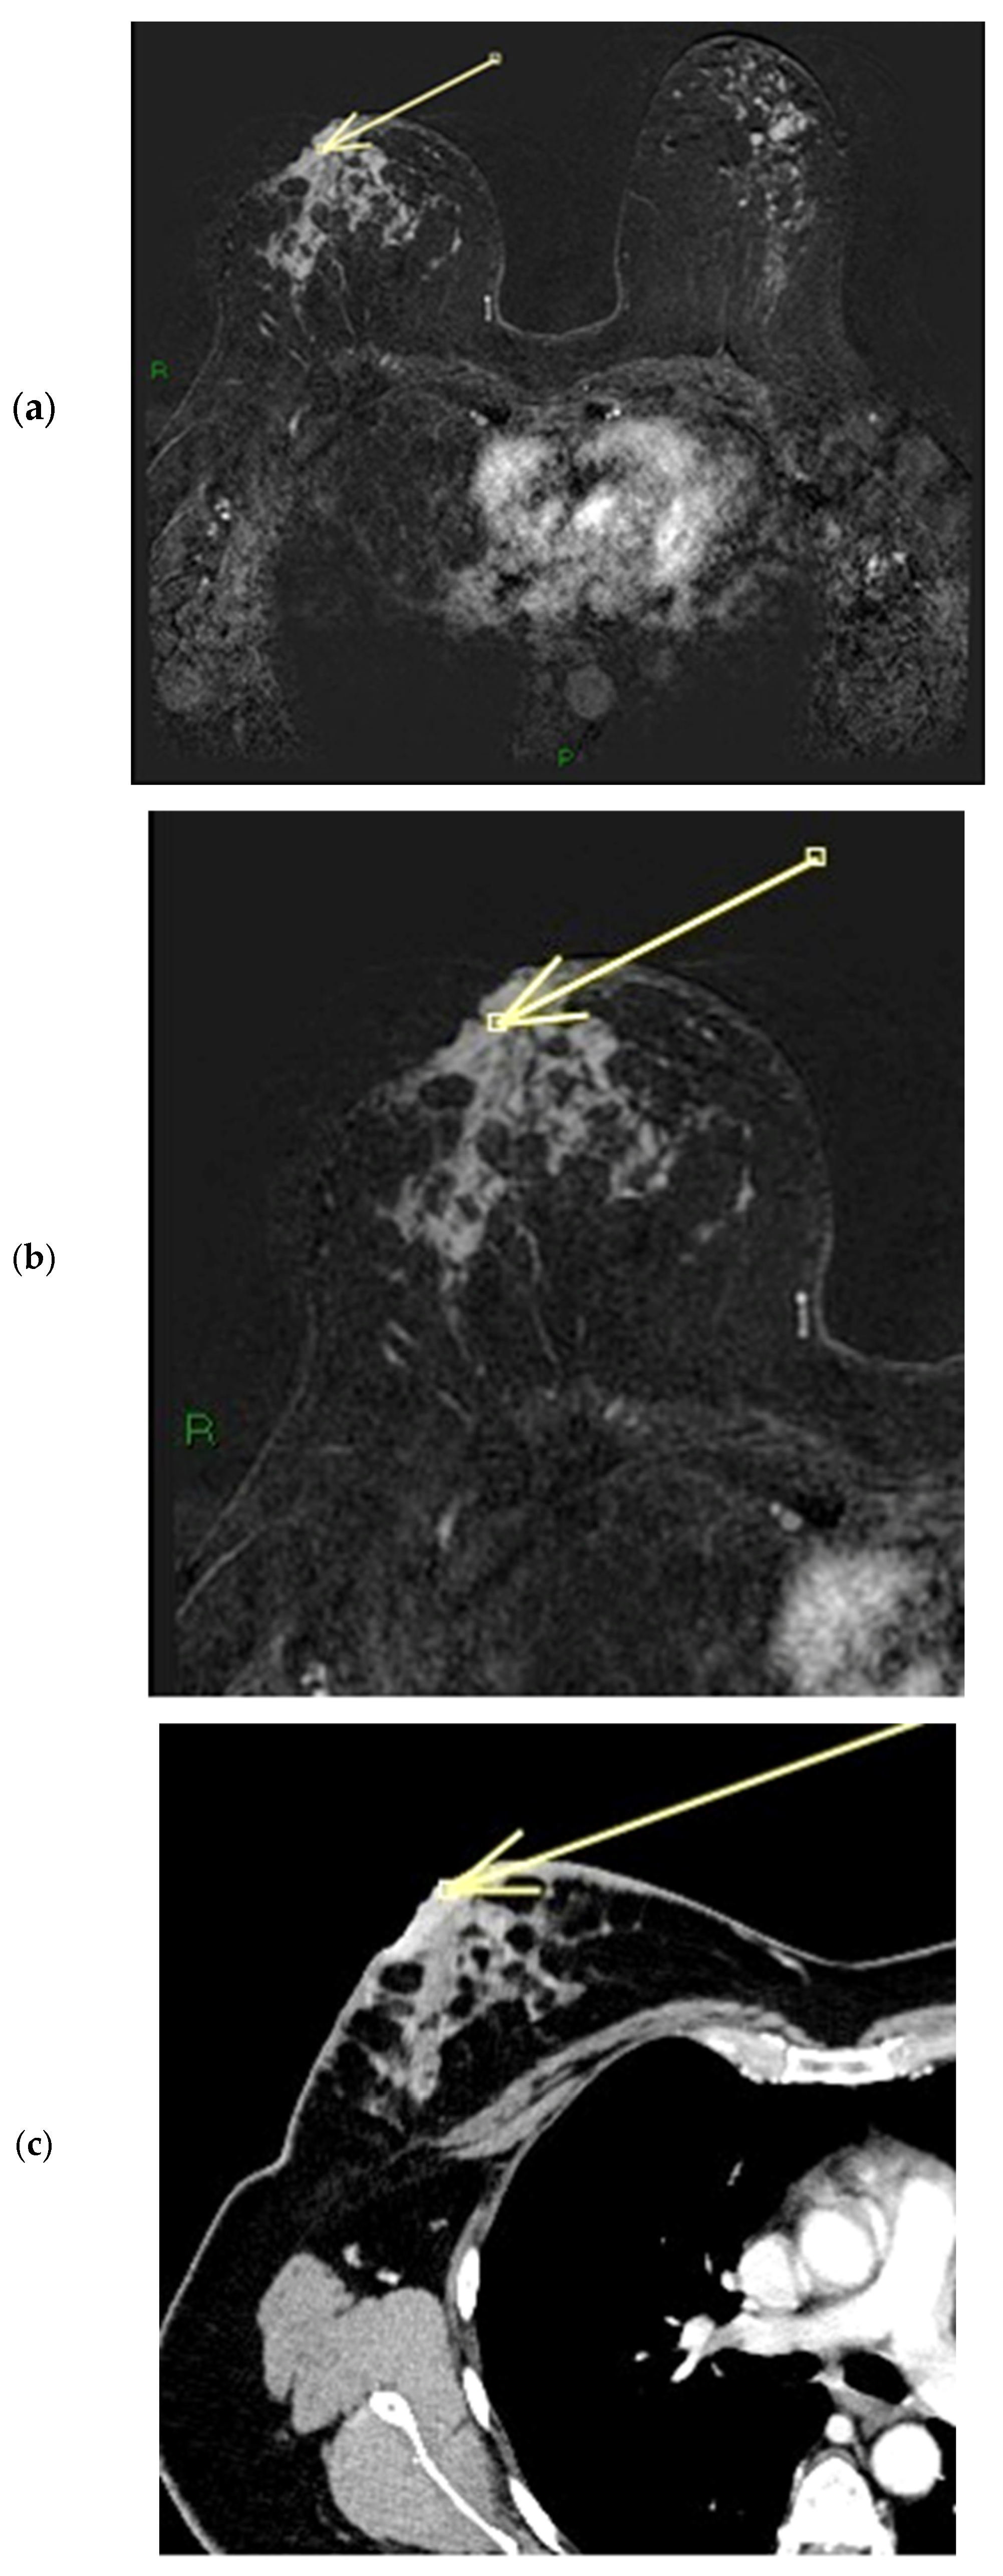

Figure 11.

(a–c) Patient’s name V.F. During ce-MR, we notice a flat thickened right nipple, with the representation of SLE, NEZ, and marked patchy INE pattern of enhancement (a). In the ce-T1 sequence (a) and in the MIP reconstruction (b), we can observe the presence of a partly necrotic mass-like enhancement of at least 6 cm located in the external quadrants of the right breast; the non-mass-like enhancement component that infiltrates the nipple measures approximately 3 cm and extends anteriorly to the gross mass (arrow in a). In the ce-CT scan, the arrow shows enhancement of both the base and the body of the right nipple. Morphology is flat, with skin thickening associated (c).